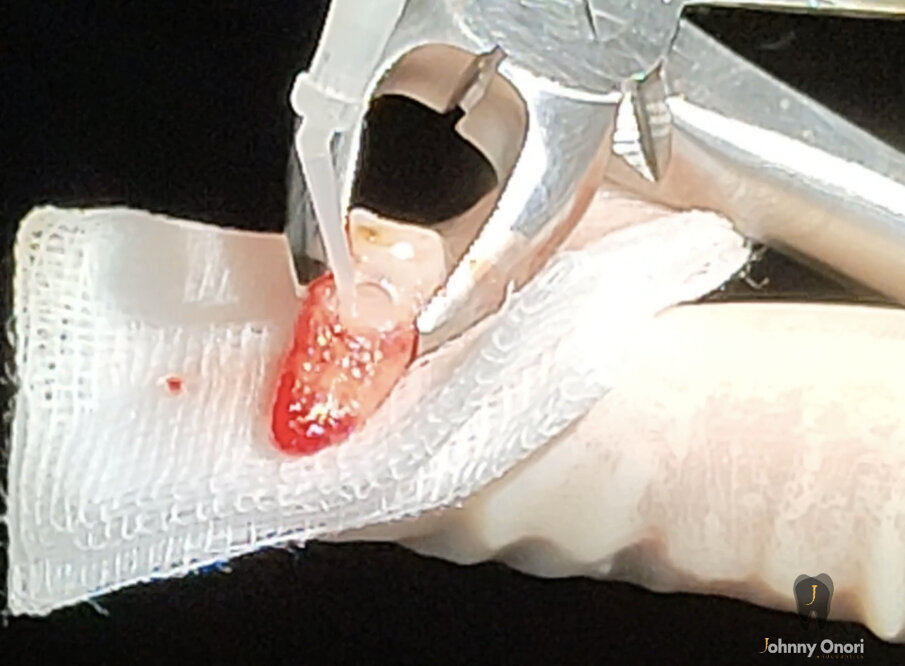

La CBCT è uno strumento utile in endodonzia, utilizzato per valutare l’entità del difetto di riassorbimento cervicale esterno, per rilevare e classificare la parodontite apicale e per valutare i riferimenti anatomici con maggiore precisione. Diversi autori hanno dimostrato che la CBCT è molto utile nella diagnosi di questo tipo di riassorbimento2-4. Nel caso clinico presentato, sono state osservate una lesione apicale e un ECIR, e la CBCT è stata utilizzata per osservare la dimensione della lesione periapicale e la dimensione e la localizzazione del difetto di riassorbimento nei tre livelli spaziali. Diversi fattori intervengono nella guarigione della parodontite apicale dopo l’intervento chirurgico periapicale, come la profondità della retro-preparazione apicale, che deve essere di almeno 3 mm, il materiale scelto per la retro-otturazione e il tempo di follow-up. Ulteriori scansioni CBCT sono state necessarie in questo caso per confermare la completa guarigione della lesione. L’estrusione chirurgica intenzionale è stata tentata con lo stesso trattamento chirurgico minimamente invasivo5, 6. Il tessuto di granulazione del difetto di riassorbimento è stato rimosso e l’area è stata sigillata con acido tricloroacetico al 90% e riempita con un cemento ionomero nano-ibrido di resina idrofila a doppia polimerizzazione (Geristore, DenMat; Figg. 4a, 4b). La chirurgia apicale è stata poi eseguita a 3 mm utilizzando le punte ultrasoniche del kit di chirurgia apicale EndoSuccess (ACTEON). La retro-otturazione è stata eseguita con un cemento minerale a triossido aggregato (CeraPutty, Meta Biomed), e il dente è stato riposizionato all’interno dell’alveolo, splittato con filo intrecciato semiflessibile per quattro settimane (Figg. 5a-5d)7, 8. Dopo sei mesi, è stata eseguita un’altra scansione CBCT per valutare la guarigione. Si è osservata una risoluzione quasi completa della lesione periapicale (Fig. 6). Anche la situazione intraorale sembrava buona, e non c’erano segni di patologia apicale sulla radiografia periapicale, che ha anche mostrato la guarigione quasi completa (Fig. 7). Il dente è rimasto asintomatico.

Figg. 4a, 4b - Estrusione chirurgica e sigillatura del riassorbimento. L’acido tricloracetico è stato applicato con un batuffolo di cotone per rimuovere tutto il tessuto riassorbitivo (a). Infine, la cavità è stata riempita con Geristore (DenMat) (b).

Figg. 4a, 4b - Estrusione chirurgica e sigillatura del riassorbimento. L’acido tricloracetico è stato applicato con un batuffolo di cotone per rimuovere tutto il tessuto riassorbitivo (a). Infine, la cavità è stata riempita con Geristore (DenMat) (b).